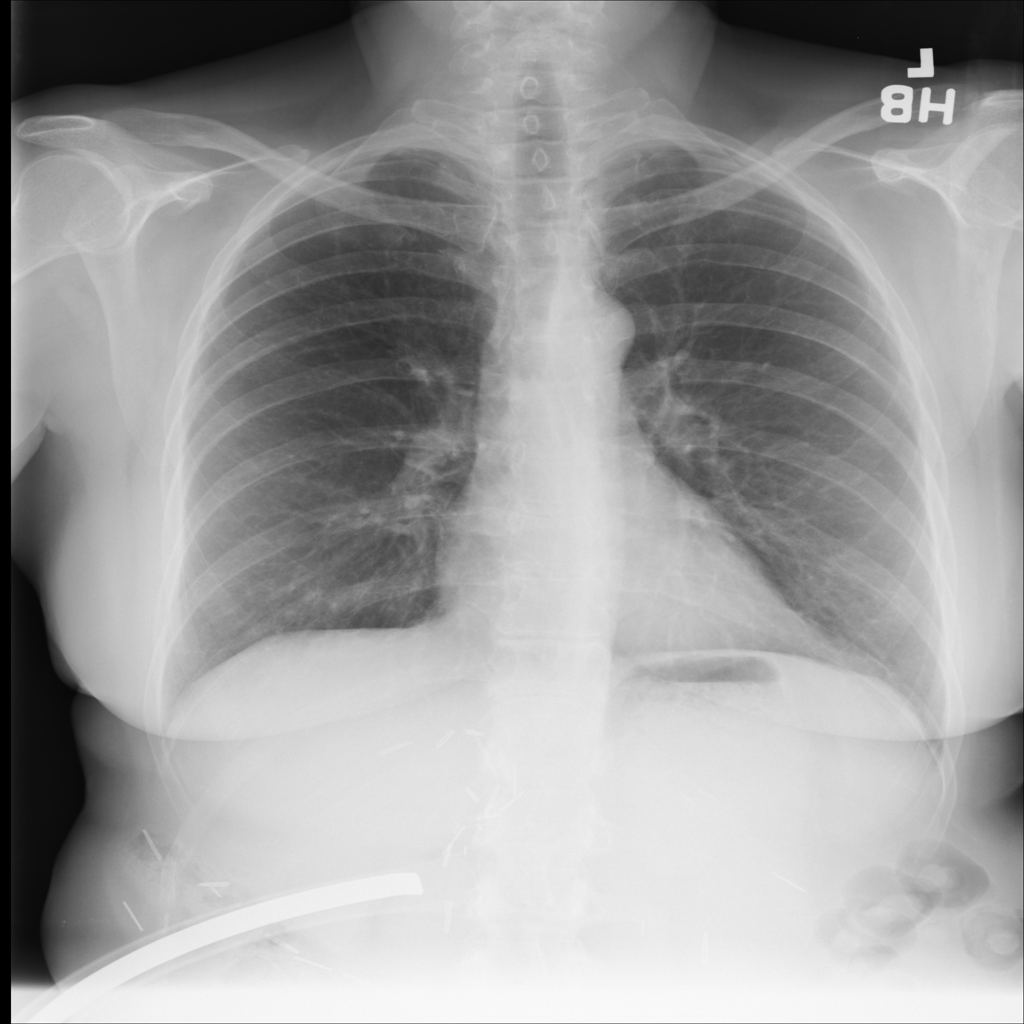

PAT-0ABD · IMG-000Hernia

PAT-0ABD · IMG-000

PA